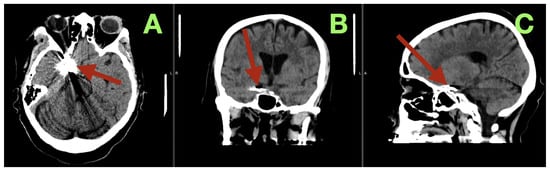

During the vasospasm-risk period, serial transcranial Doppler studies of the patient’s right middle cerebral artery (MCA) velocities ranged from 85 to 105 cm/s, and her fetal PCA (fPCA) velocities ranged from 55 to 70 cm/s, indicating that there was no clinically relevant vasospasm detected sonographically. On the fifth postoperative day, non-contrast CT (Figure 3) imaging confirmed the stable position of the clip, no interval hemorrhage, no territorial hypodensities, no interval change in the configuration of the ventricles, and no interval hydrocephalus. Additionally, the basal cisterns remained open, and the basal ganglia were normal in appearance.

Figure 3.

Postoperative day 5 non-contrast CT. (A) Axial section at the level of the skull base demonstrates the aneurysm clip at the right carotid–posterior communicating region (arrow), with expected localized metallic artifact and no evidence of recurrent subarachnoid hemorrhage, new intraparenchymal bleeding, or territorial hypodensity. The surrounding basal cisterns at this level remain discernible, without mass effect. (B) Coronal reconstruction confirms stable clip position within the right parasellar and suprasellar corridor (arrow), with preserved ventricular configuration and no radiographic signs of acute hydrocephalus or midline shift. (C) Sagittal reconstruction localizes the clip construct along the intended carotid–posterior communicating junctional plane (arrow), demonstrating anatomical coherence of the skull-base region and absence of secondary compressive changes.